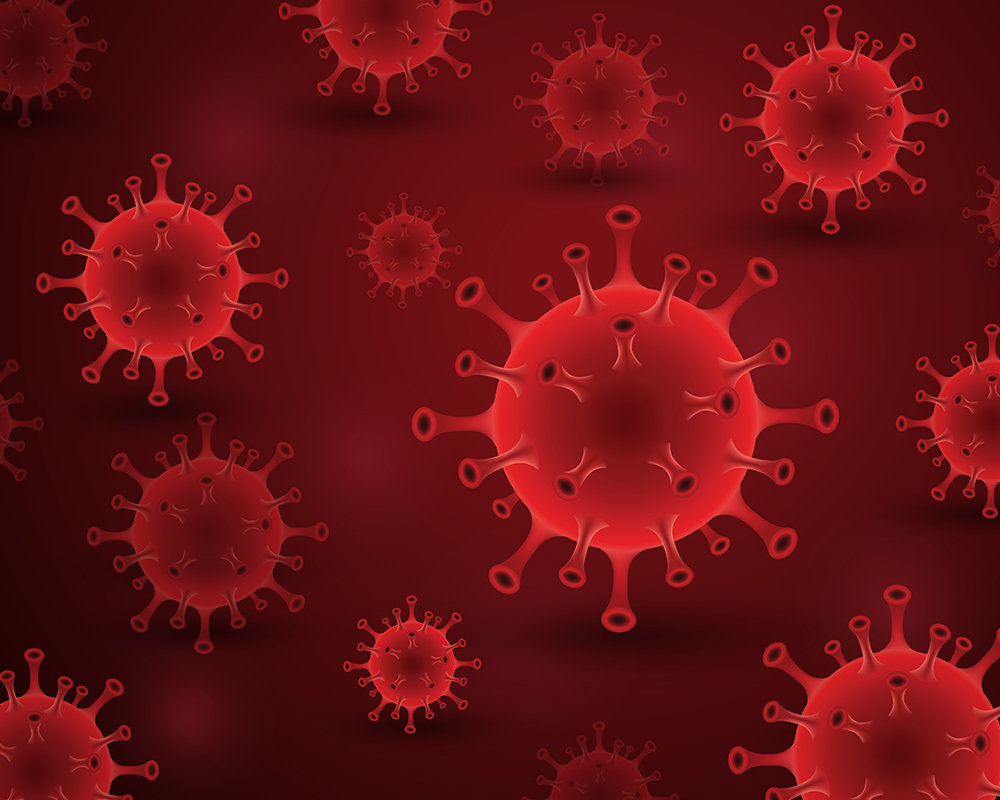

कोविड-19 के नए लक्षण 2025 में: कौन से लक्षणों को नज़र अंदाज़ न करें?

कोविड-19 महामारी की शुरुआत 2019 में हुई थी, और अब 2025 में भी यह वायरस पूरी तरह गया नहीं है। समय के साथ-साथ वायरस ने अपने रूप बदले हैं और हर नए वेरिएंट के साथ इसके लक्षणों में भी बदलाव

Understanding the HMPV Virus: A Guide for Jaipur Residents

The recent rise in Human Metapneumovirus (HMPV) cases, particularly news of the HMPV virus in India and reports from China has caused concern. This blog provides comprehensive information about HMPV, specifically addressing the situation in Jaipur, Rajasthan. We’ll answer frequently

कोविड-19 के नए लक्षण 2025

कोविड-19 महामारी की शुरुआत 2019 में हुई थी, और अब 2025 में भी यह वायरस पूरी तरह गया नहीं है। समय के साथ-साथ वायरस ने अपने रूप बदले हैं और...

Understanding the HMPV Virus: A

The recent rise in Human Metapneumovirus (HMPV) cases, particularly news of the HMPV virus in India and reports from China has caused concern. This blog provides comprehensive information about HMPV,...